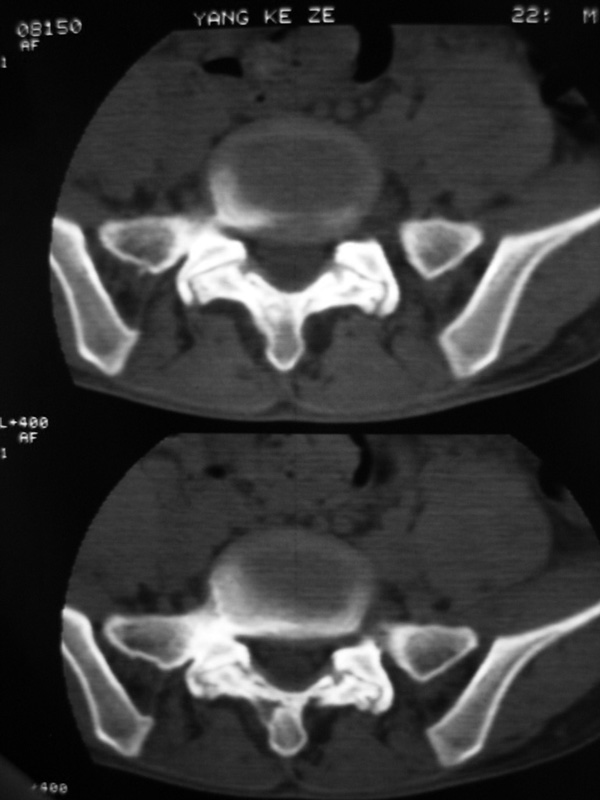

以下是引用w_jianhua在2007-3-8 11:14:00的发言:[br]椎小关节及右侧骶髂关节关节面毛糙,间隙不规则狭窄,骨皮质增生硬化,支持强直性脊柱炎,并椎间盘膨出

以下是引用fumaogui在2007-3-8 8:40:00的发言:[br]腰椎椎间关节增生硬化,关节间隙变窄,右侧骶髂关节间隙变窄,关节面硬化[br]考虑强直性脊柱炎.建议结合化验查:c--反应蛋白和类风湿因子.